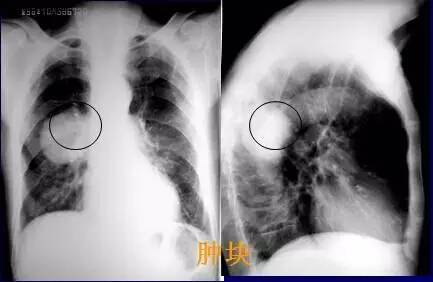

基础篇!肺部常见病变的x线片总结

肺癌x光片图片晚期

肺癌x光片图片

肺癌x光片图片早期

肺部x光片

肺部x光片怎么看

肺部x光片阴影